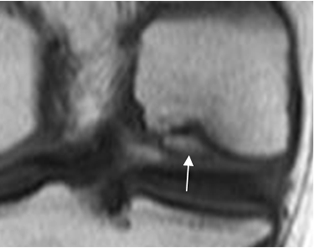

Fig 207. Lesión osteocondral tipo 4.

RM coronal en T1. Lesión osteocondral con fragmento desprendido, pero no desplazado.